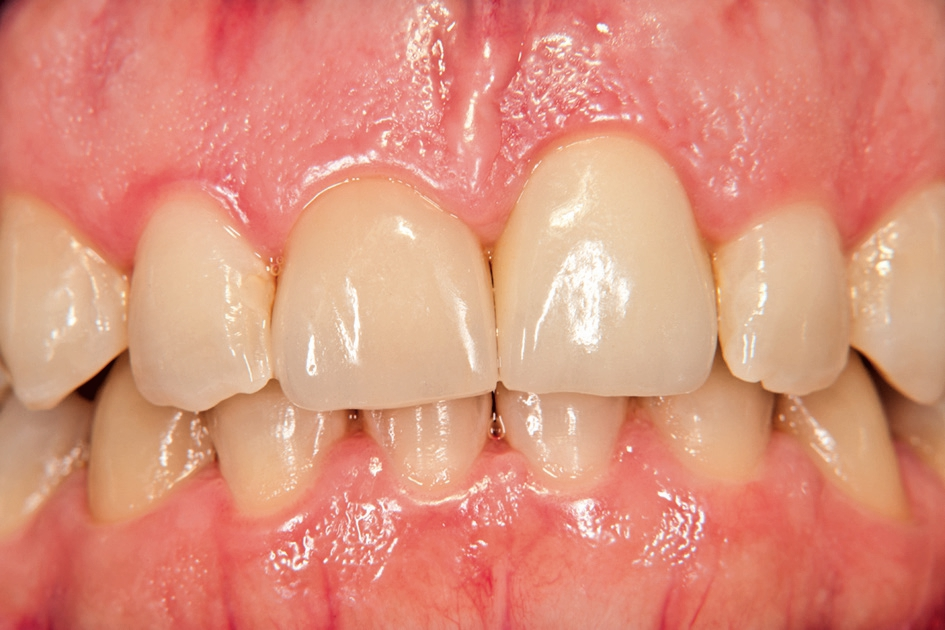

Gleichzeitig mit der prothetischen Versorgung des Implantats wurde auch für Zahn 11 ein Veneer geplant. Zum Einsatz kam ein Zeramex T Implantat Durchmesser 5,5 mm, Länge 12 mm. Für die Kronenversorgung wurde ein mit e. Max überpresstes CAD-Abutment gewählt. Während der Einheilphase des Implantats kam eine Sunflex-Prothese zum Einsatz.